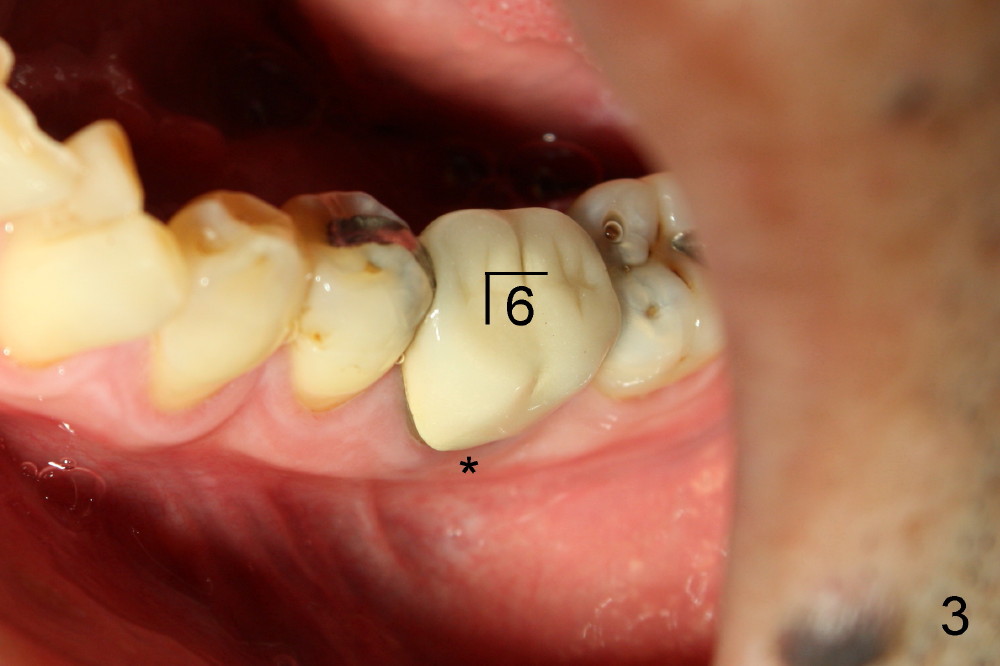

一两年前吴先生右下第一磨牙植牙偏舌侧(图一颊侧观,*:颊侧牙槽骨凹陷;图二镜影观,*:舌侧暴露植牙(光滑部分),但是他非常满意,他的论点是我们应该趁年轻,换所有该换的器官(包括牙齿)!

检查证实左下六颊侧骨板没有萎缩(图三,与图一对比),是立刻植牙适应症。不过根分叉牙龈没有红肿,探诊没有触痛,问病人疼痛性质,“刺痛”,再次仔细检查左下象限(图三),发现一个问题。那是什么呢?